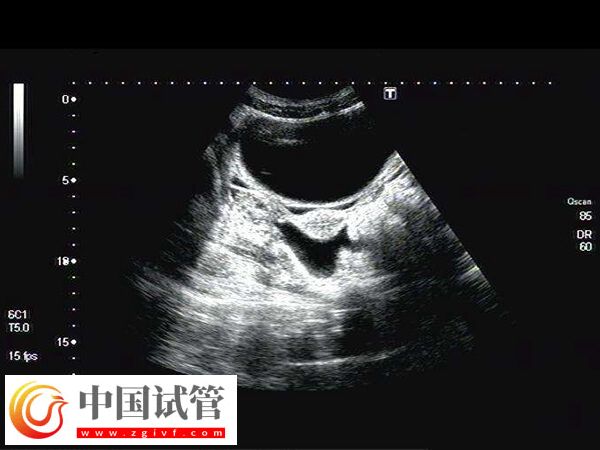

子宫动脉阻力高通常是指子宫动脉的血流受阻,这时子宫的血液供应不足,可能会引起局部缺氧和营养供应较差,如果此时进行移植,可能易发生胚胎停育、发育迟缓等情况,因此为改善此情况,患者在移植前可注射肝素,至于具体打多久时间,如下所示。

患者做试管婴儿移植前,如果发现有子宫动脉阻力高的情况,一般是在胚胎移植前2-5天左右打肝素制剂,这样的注射时间通常有利于药物的吸收利用,并改善子宫内膜血供,从而改善子宫动脉阻力高症状。

子宫动脉血流阻力高的试管患者,通常在移植前7天左右打肝素,可以治疗因此而易发生的栓症,同时还能提高母体的免疫力,为试管移植做好准备,让胚胎更好地植入和生长发育。